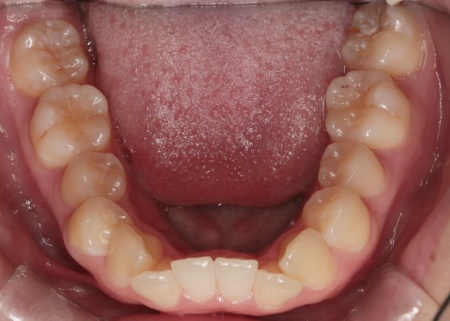

20代女性 乱れた上下の歯並びをハイブリッド矯正で改善した症例

拝見したところ、上下の歯はデコボコに生えている状態でした。

このままでは見た目が気になるだけでなく、磨き残しが起こりやすくなることで虫歯や歯周病などの発症リスクが高まります。